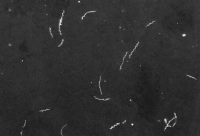

Unter einer nicht zu unterschätzenden Anzahl verschiedener zeckenübertragener Erkrankungen ist in Mitteleuropa die Lyme-Borreliose die häufigste [1, 2]. Erreger der Erkrankung ist Borrelia burgdorferi, ein Bakterium aus der Familie der Spirochaetaceae (Abb. 1). Das Verbreitungsgebiet der Lyme-Borreliose

Abb. 1: Borrelia burgdorferi im Dunkelfeldmikroskop (Vergrößerung 400-fach)